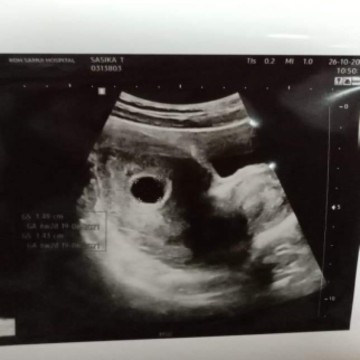

6วีคแล้ว ยังซาวด์ไม่เจอตัวเล็กเลยค่ะ แม่ๆ มีใครเจอเหตุการณ์นี้บ้าง#ขอคำแนะนำหน่อยค่ะ #ขอบคุณสำหรับคำตอบค่ะ

ของเรา7-8สัปดาห์ไม่เจอหมอบอกท้องลม พึ่งเสียน้องไปได้1อาทิตย์คะ เดี๋ยวก็เจอนะคะรออีกหน่อยอายุครรภ์ยังน้อยอยู่เลย สู้ๆคะ🥰